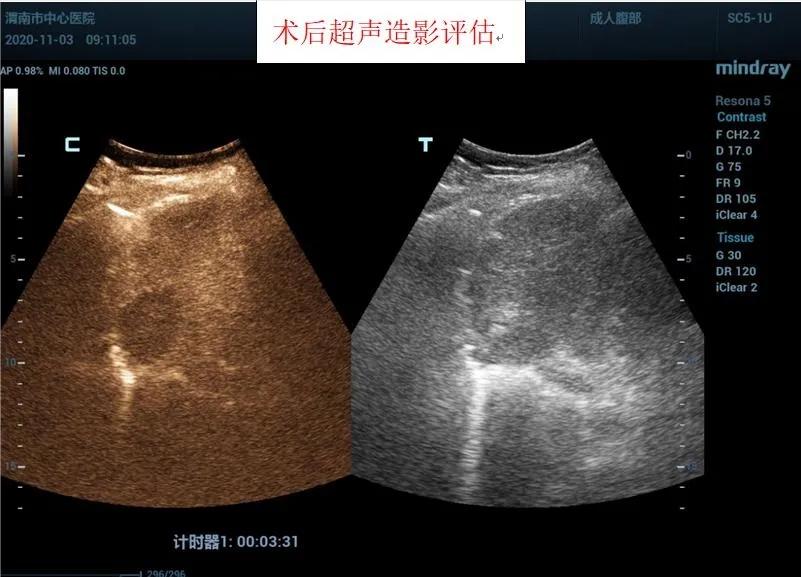

在王建宏教授的指导下,华玺副主任医师、韩婷婷主治医师的默契配合下,经过20余分钟,手术顺利完成,术后安返病房。术后3天超声造影进行评估,显示消融处呈无增强,提示达到预期治疗效果且患者精神状态良好。